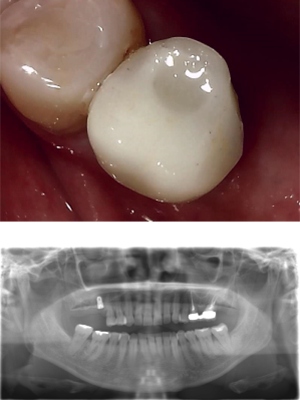

30代 女性 奥歯 インプラントGBR

| 年代・性別 | 30代・女性 |

| 治療回数 | 1回 ※術前治療・検査除く |

| 治療期間 | 5ヶ月 |

| 料金 | ¥60,000(税込) |

GBR(Guided Bone Regeneration:骨再生誘導法)とは、インプラント治療において、骨の厚みや高さが足りない場合に行う歯槽骨を再生する方法です。骨量不足の患者様でも、骨造成を行うことでインプラントの埋入に必要な骨の高さや厚みが得られます。 GBR(再生誘導法)は、骨が痩せて十分な骨量が確保できない患者様に、骨の再生によってインプラントの埋入を可能にする治療方法の一つです そのような骨が欠損した部分では、骨を作る「骨芽細胞」よりも、骨にならない「線維芽細胞」の方が増殖しやすいという特徴があります。そのためGBRでは、骨形成の妨げになる繊維芽細胞の侵入を防ぐため、骨を増やしたい部分を「メンブレン」という人工膜で覆い、その中に自家骨や人工の骨補填材を詰めて骨芽細胞の増殖を促します。 |

| 副作用 | 術後に腫れ・痛みが出る可能性がある。 |